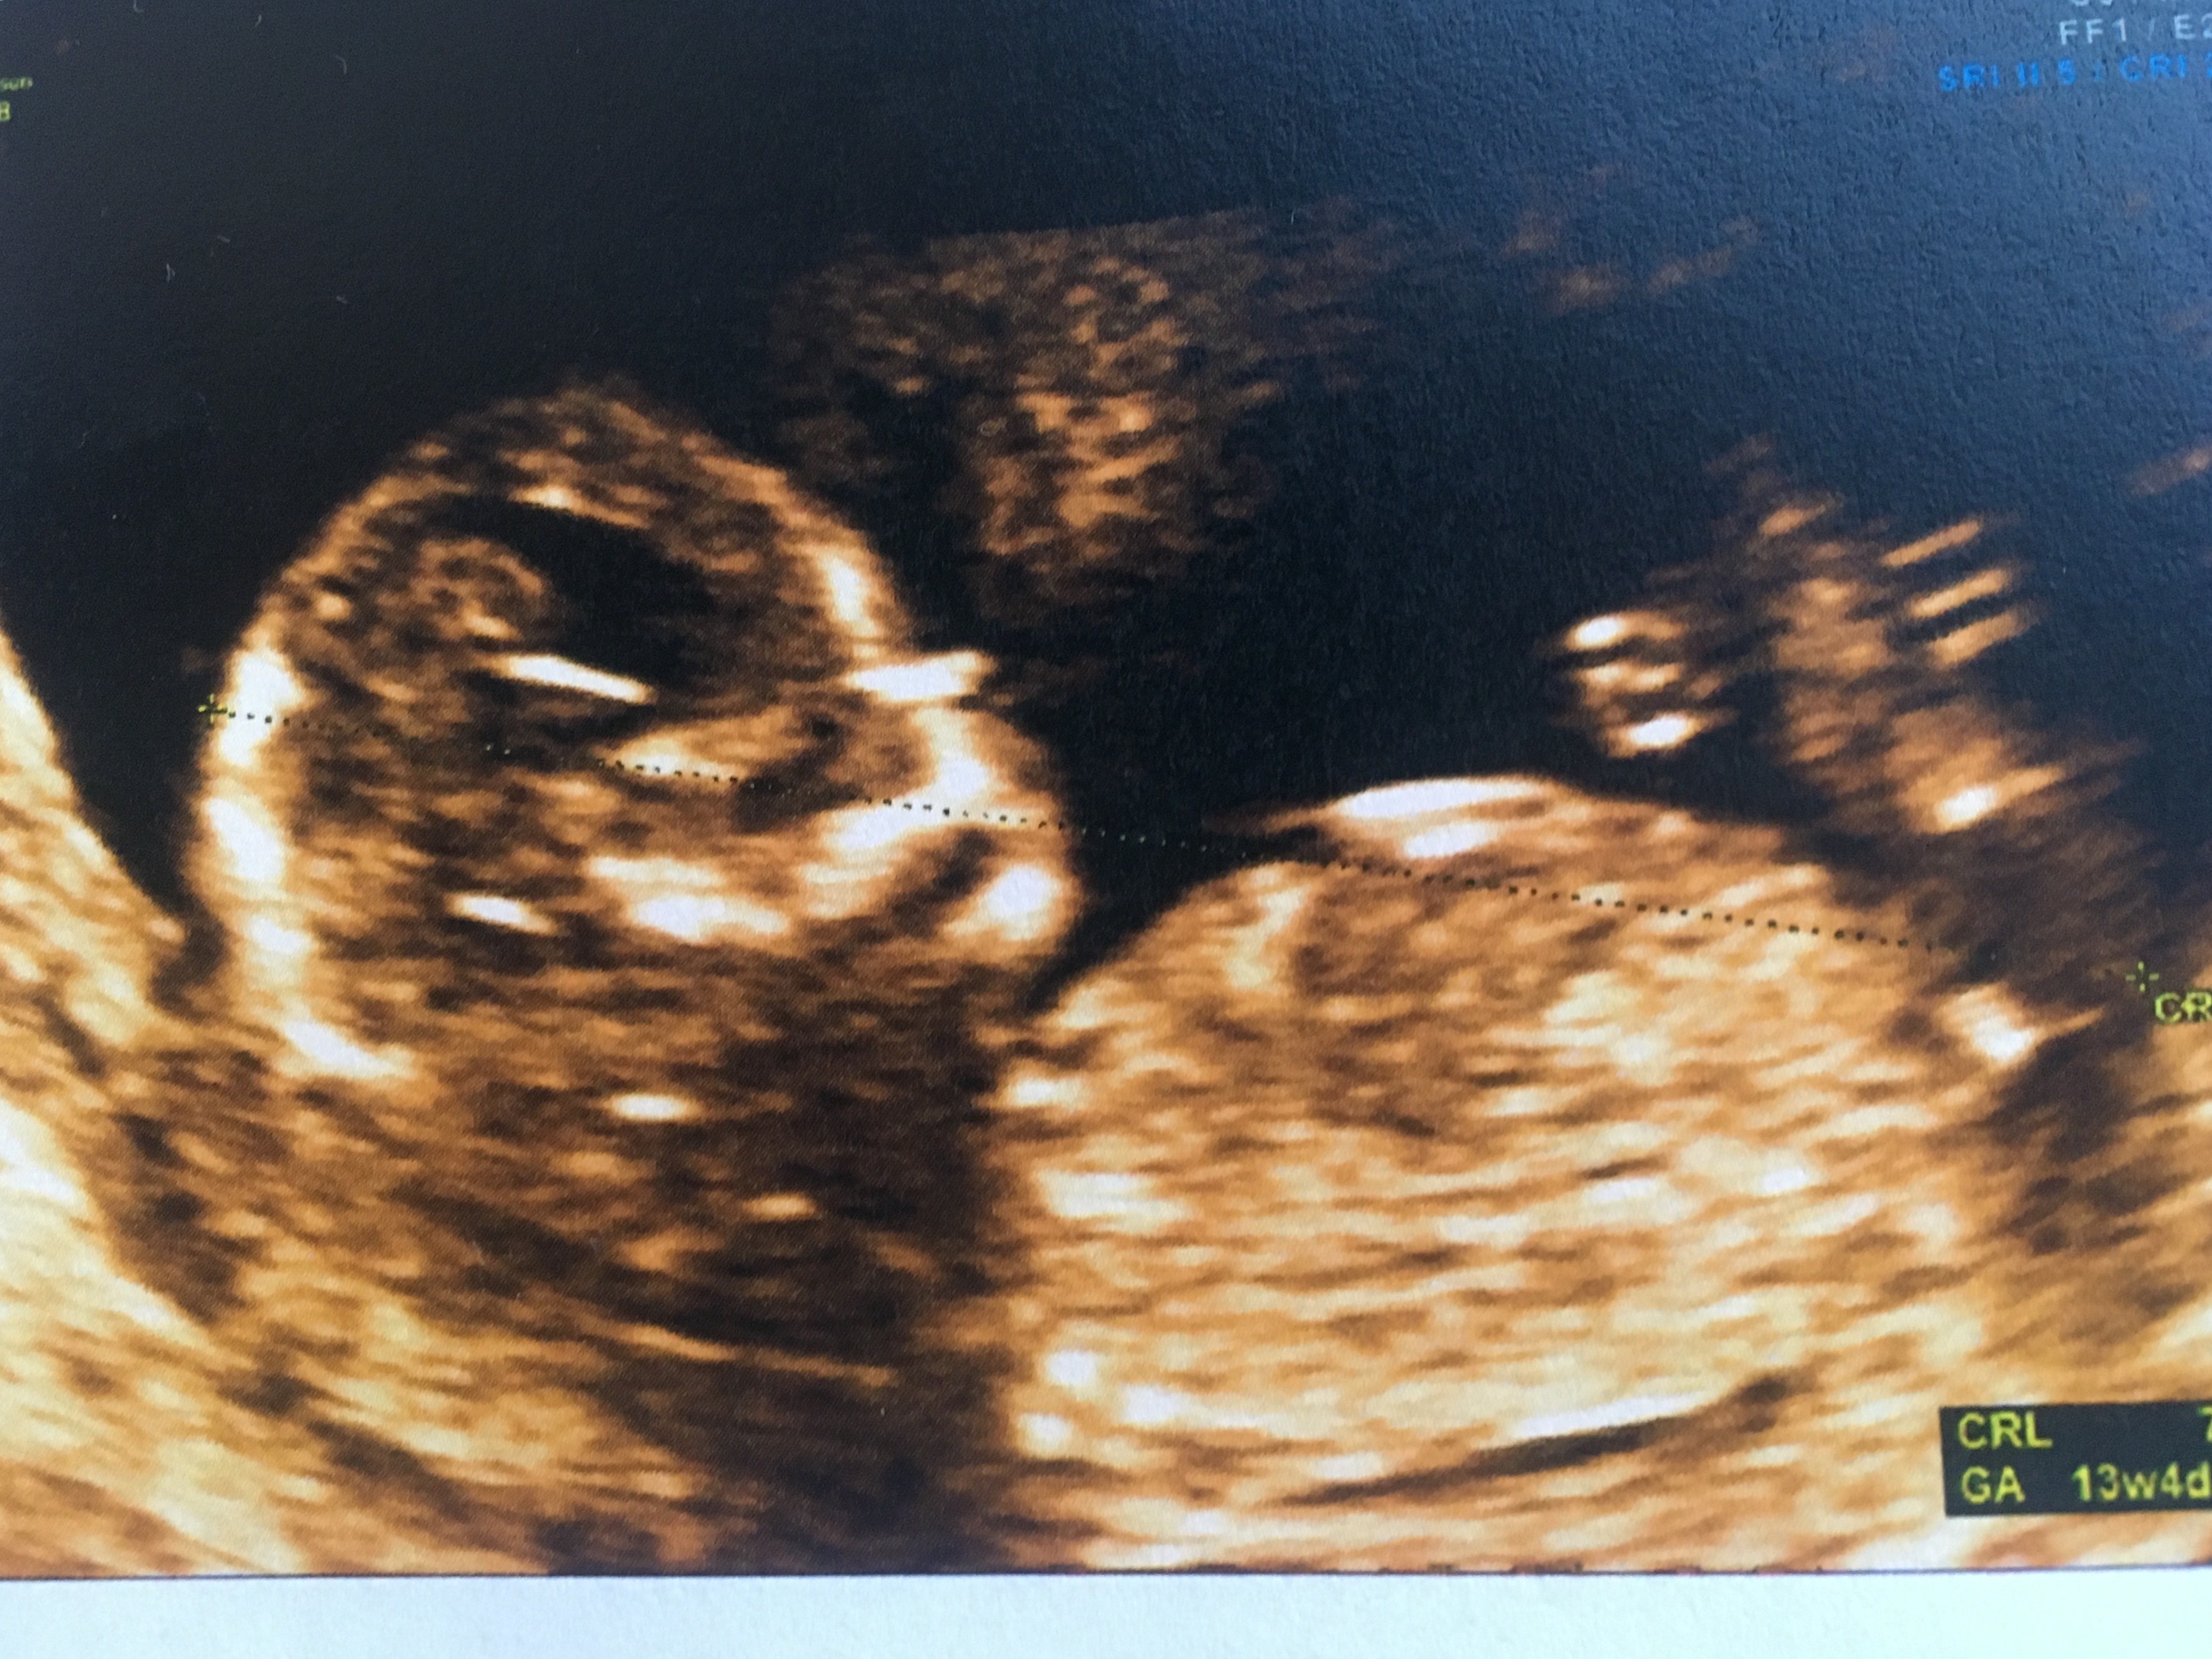

Jeszcze mam coś takiego również z 12+5 ale nie wiem czy coś widać

Pozdr, z góry dziękuje za wszystkie sugestie.

Załączniki

• 3D63C558-5FF5-4B8E-80AB-230D931DE304.jpeg

3D63C558-5FF5-4B8E-80AB-230D931DE304.jpeg

866,3 KB · Wyświetleń: 328